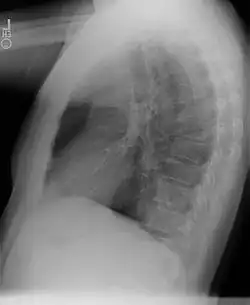

Séquestration pulmonaire

Radiographie d'une séquestration pulmonaire

Une séquestration pulmonaire, aussi appelée séquestre pulmonaire[1], est une malformation congénitale du poumon où une partie du tissu pulmonaire n'est pas connecté à l'arbre bronchique ni à la circulation vasculaire pulmonaire[2].